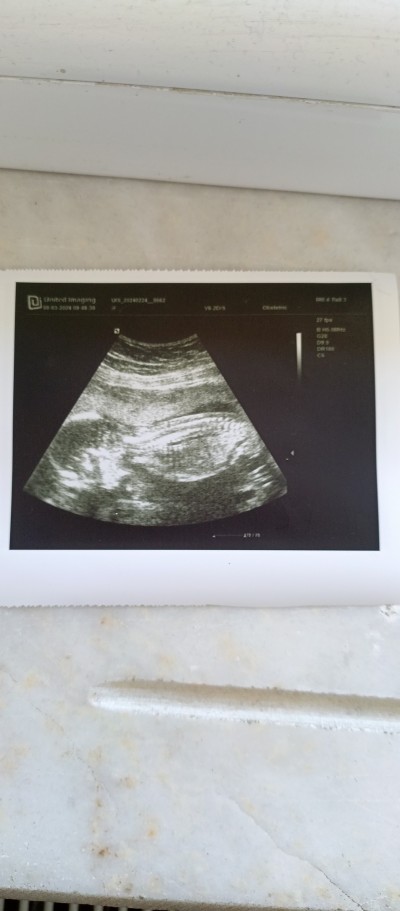

Cinisyet tahmini yapar mısınız lütfen

Hiç anlamıyorum ama erkek hissettim

Kaç haftalık cnm doktor tahmin etmedi mi ben kız hissediyorum.

Bana kiz gibi geldi cnm

Burda bebeğin kafası ve gövdesi gözüküyor sadece. Ben 16haftada öğrenmişdim. Sağlıcakla gelsin inşAllah

Kız bu kızzz

Üzü donük aşağı oyuzden